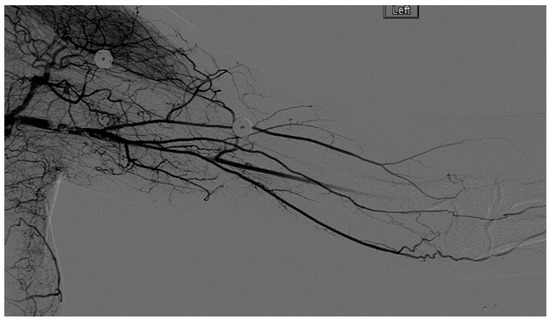

A heparin drip was then initiated, and she was taken to the catheterization lab for thrombolysis. This was carried out with Alteplase for 48 h as the patient had strong collaterals and was not in limb-threat (Figure 7, Figure 8, Figure 9, Figure 10 and Figure 11). However, her radial artery remained occluded. She was then taken to the operating room for thromboembolectomy of the left brachial and radial arteries (Figure 12). She was continued on anticoagulation post-operatively and was discharged.

Figure 9.

Distal left arm angiography in an ATOS patient demonstrating an occluded radial artery at the origin and ulnar artery at the mid-forearm.